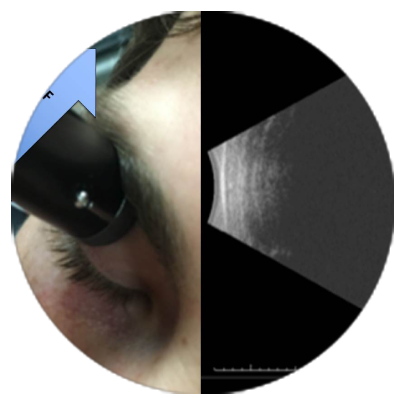

Ultrasound A and B Scan: These are imaging tests that use sound waves to create pictures of the structures inside your eye. They are painless and take about 30 minutes. The A-scan ultrasound evaluates the eye's dimensions. The retina and other components in the back of your eye may be clearly seen on a B-scan. The whole process (including the A and B scans) should take no more than half an hour. The eye is evaluated through an A-scan. The right lens implant can then be chosen for the cataract surgery.